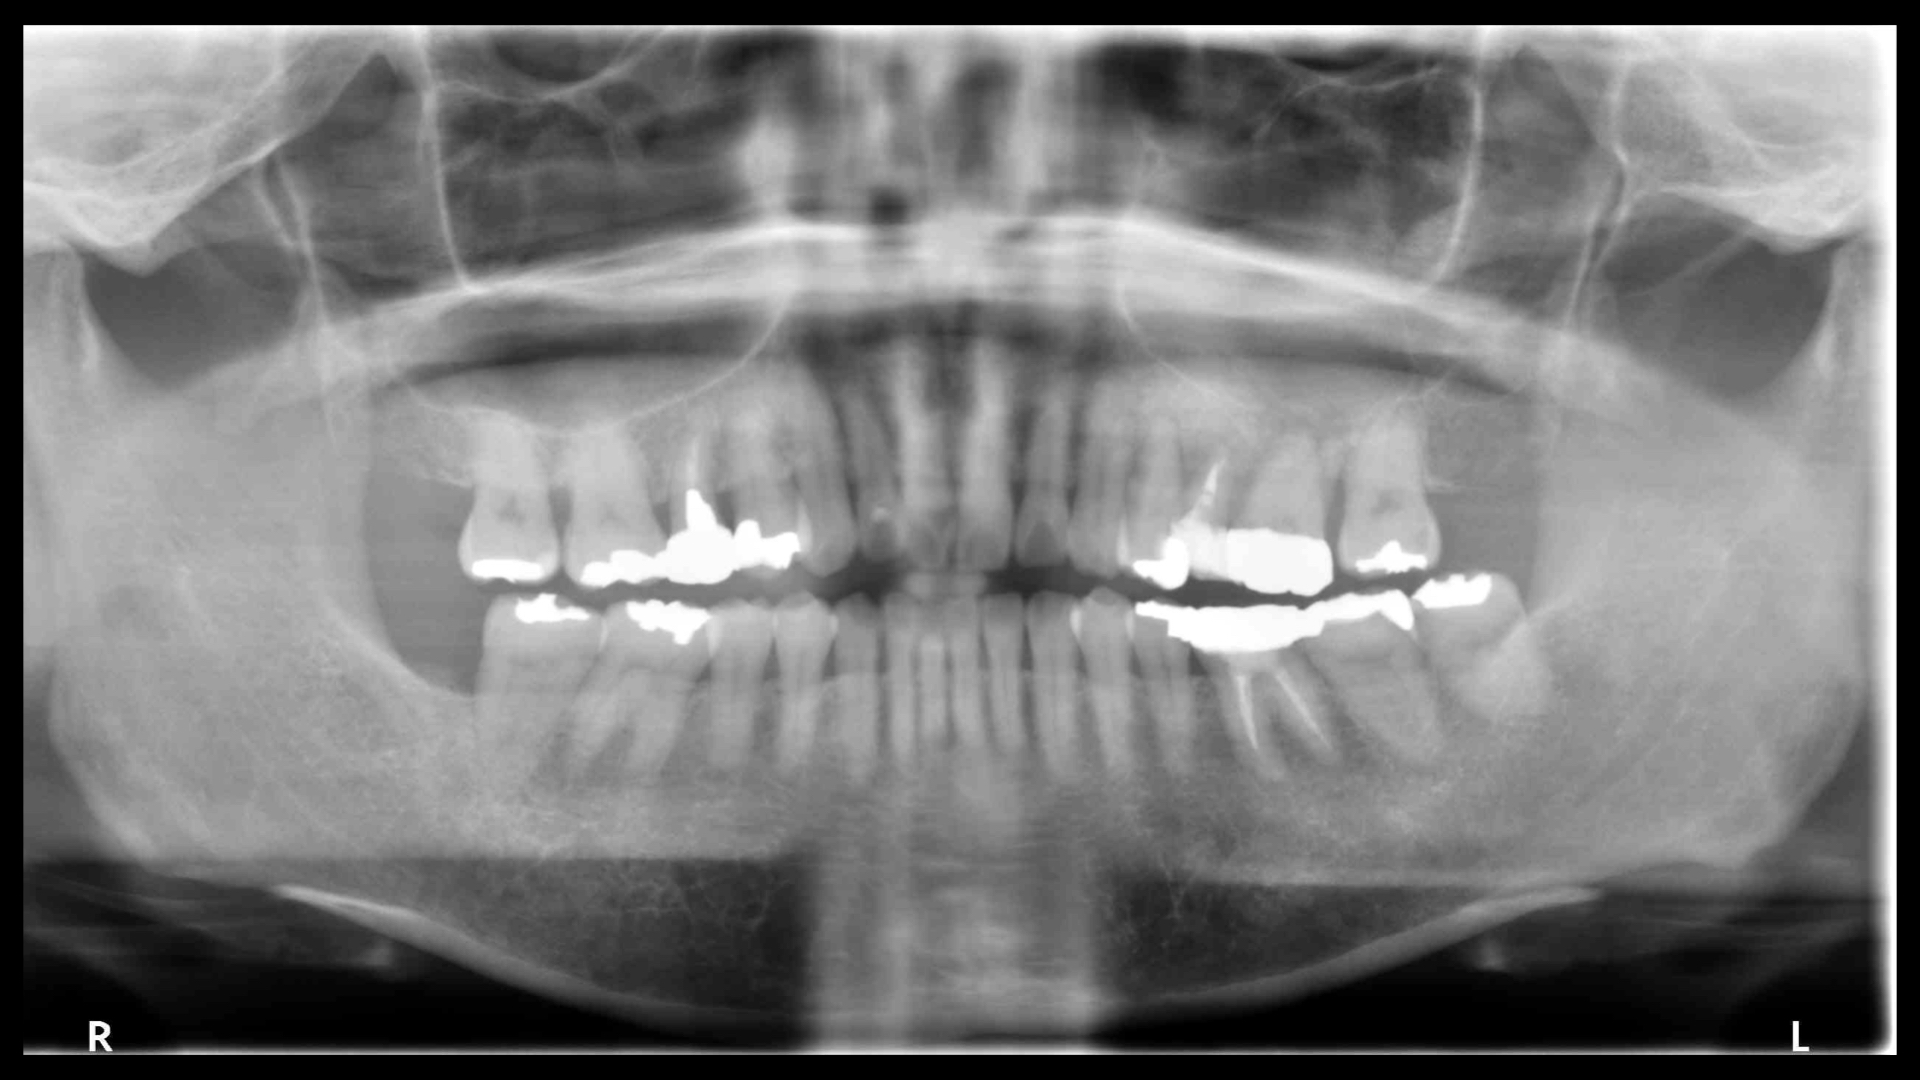

左上は支えている骨が大きく吸収しています。

歯周病の検査です。やや全体的に歯周病が進んでいますが、特に左上の部分は顕著にすすんでいます。

CT(右の画像)上では、根尖(根の先)まで骨が吸収しており、保存することが難しい状態です。

このように明らかに片方(今回は左側)のみ悪くなっているのは、歯周病の細菌だけではなく噛み合わせが悪いことによるものです。